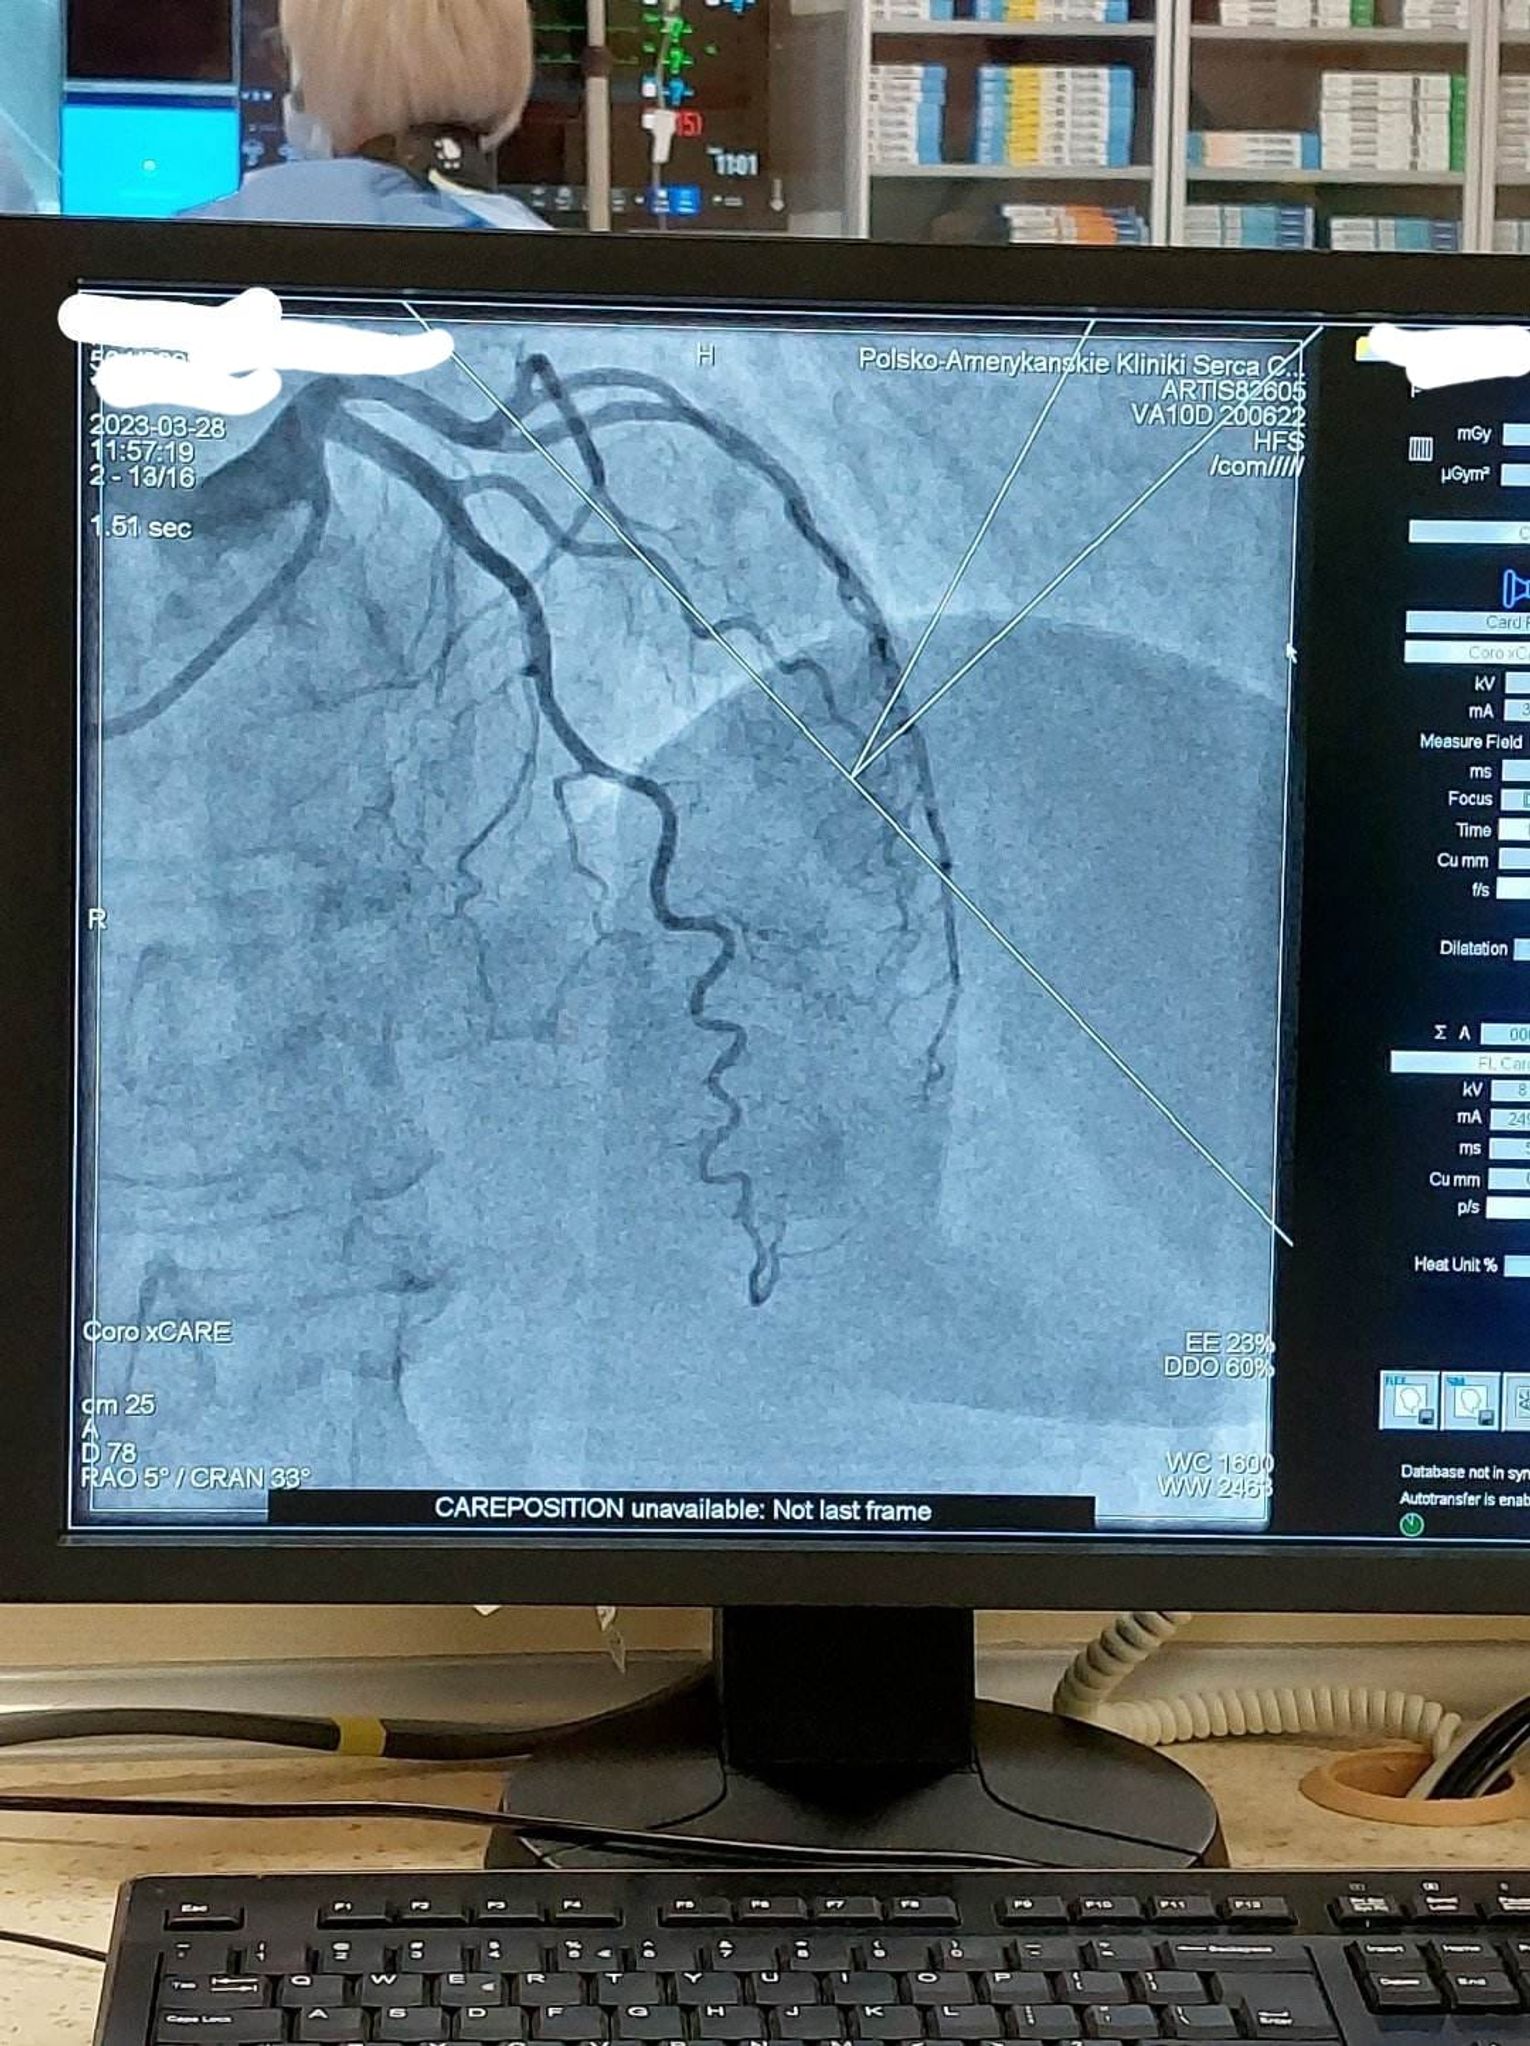

W wizycie udział wzięli: Julia Szukalska, Magda Grela i Kuba Różański oraz dyrektor szkoły Katarzyna Arciszewska-Stępień. Wyjazd był nagrodą w konkursie "Serce na dłoni" organizowanym na początku marca. Po przyjeździe uczniowie przebrali się w medyczną odzież i rozpoczęli obchód po oddziale kardiologii inwazyjnej z ordynatorem dr Januszem Prokopczukiem. Rozmawiając z personelem dowiedzieli się, jak wygląda dzień w klinice. Uczniowie mogli zobaczyć, jak przebiega zabieg wszczepienia rozrusznika serca, koronarografia, elektrokardiografia, wkłucie dożylne i przezprzełykowe echo serca. Nie zabrakło pytań dotyczących studiów na kierunku lekarskim i specyfiki pracy w tym zawodzie. Spotkanie było niesamowicie ciekawe, sprawiło uczniom wiele radości i dodało im motywacji do nauki, by spełnić swoje marzenia o studiach medycznych.

28 marca trójka uczniów II LO im. Mikołaja Kopernika w Kędzierzynie-Koźlu odwiedziła Polsko - Amerykańską Klinikę Serca w Koźlu.